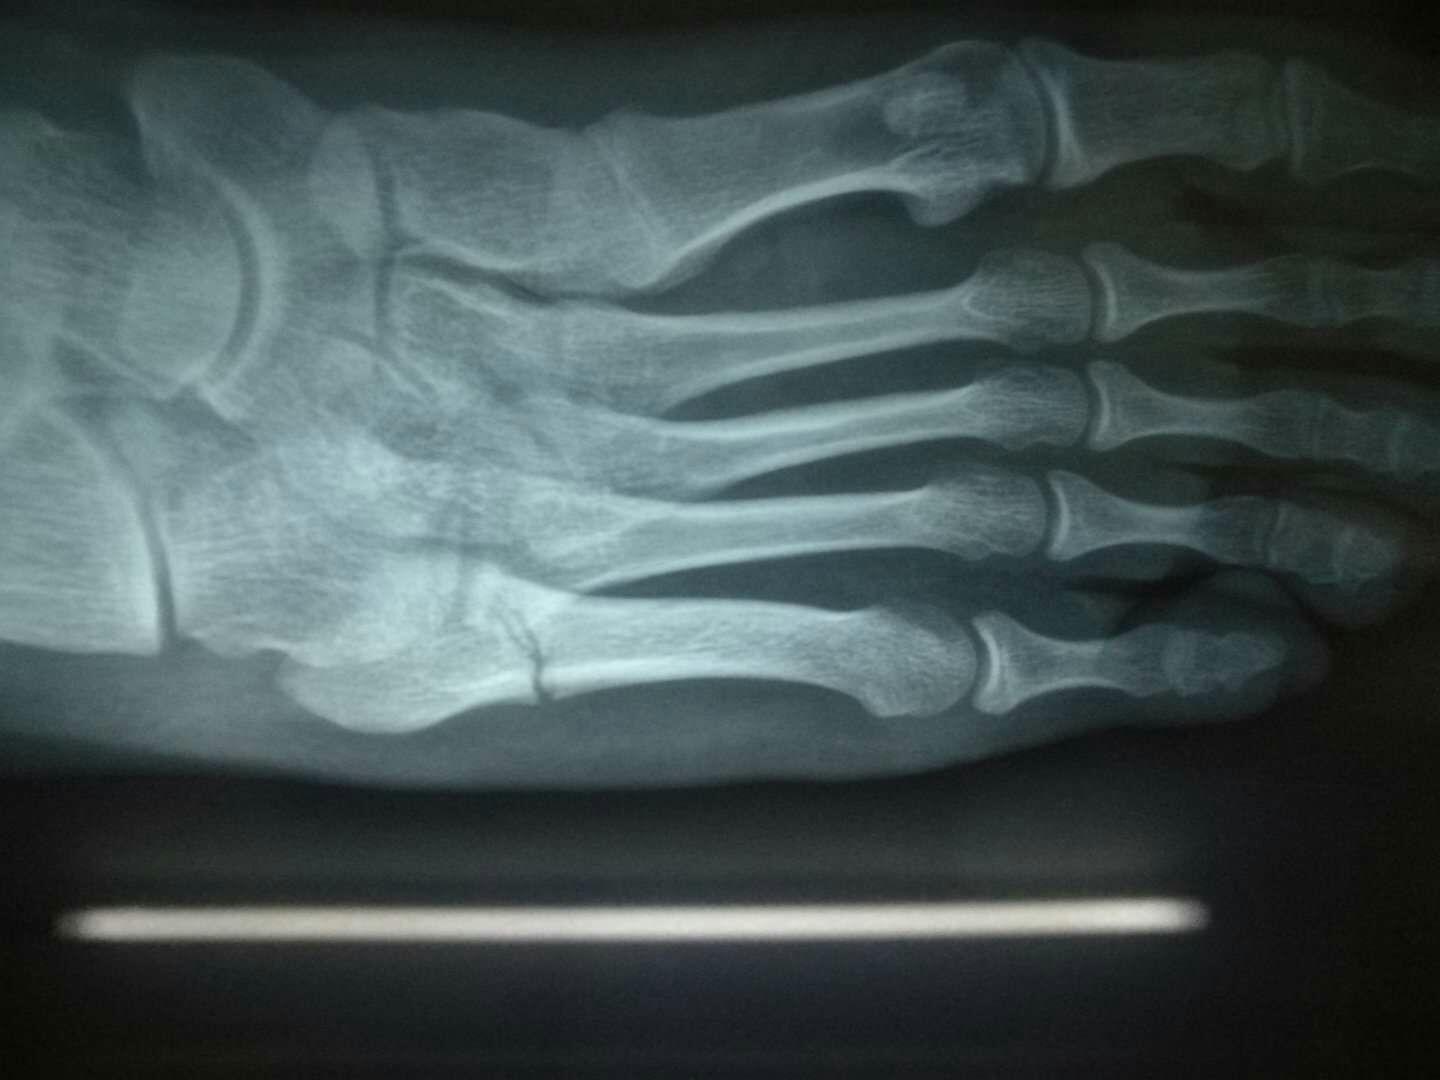

2020年年明けに左足の第五中足骨を骨折しました。結論から言うと手術し骨にボルトを埋め込みました。手術の結果、痛みが小さくなり運動等ができるようになりました。一方で折れた骨は骨片がくっついて再生することなく離れたままの状態で安定しました。治療期間約3か月、ここでは骨折.. 第5中足骨骨折とも呼ばれているジョーンズ骨折は、ジャンプによる動作やランニングなどのスポーツシーンに起こりやすい障害のことを言い、一般的な骨折に比べると自覚症状が出にくいケースがあります。 今回はジョーンズ骨折(第5中足骨骨折)の原因や主な治療法、症状や経過だけでなく.

第5中足骨骨折は、基部または骨幹部で起こります。基部に起こる骨折は別名"下駄骨折"ともいわれ、昔下駄を履いたときに足を捻り発生しやすかったためこの名前がついています。 下駄での発症以外では転倒や段差の踏み外し等が原因で起こります。 骨.. 順天堂大学医学部附属順天堂医院 整形外科・スポーツ診療科「Jones骨折・第5中足骨疲労骨折」についてご紹介します。順天堂醫院は、一貫して患者さまに何よりもまず、やさしく、安全で高度の医療を提供すべく努力しております。